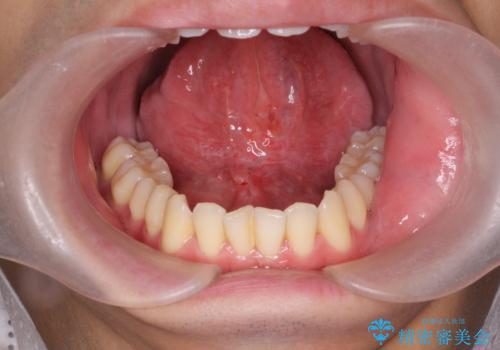

発音しづらかった、サ行・タ行・ナ行の音が改善され喜んでいただくことができました。